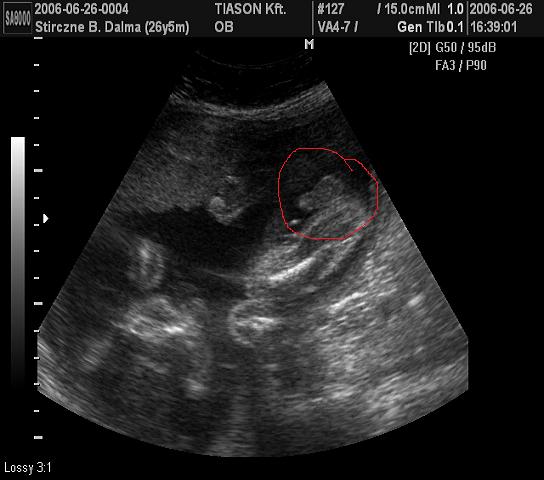

Várom a tegnapi uh eredményét

Meg képet meg mindent